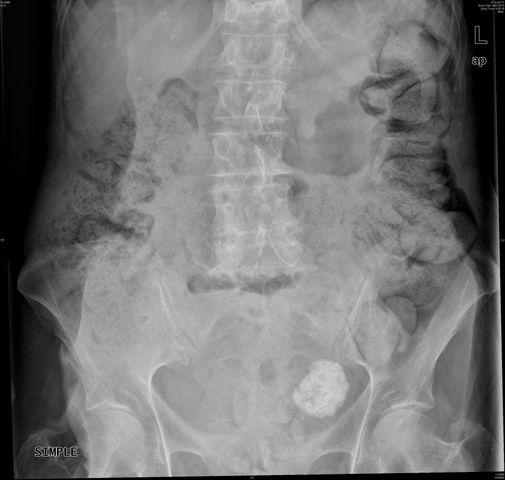

E de Paget